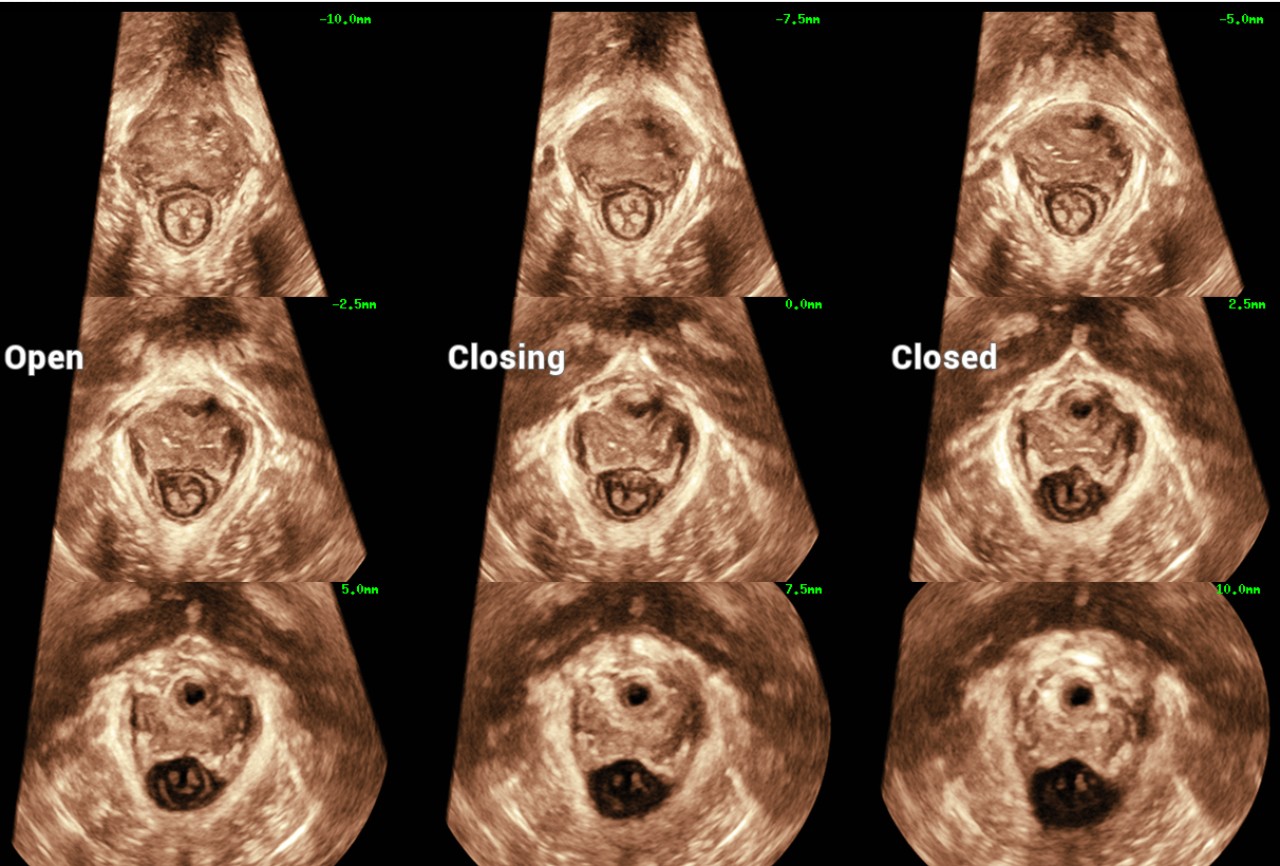

WomenŌĆÖs health is the foundation of health for all and is especially important for countries with aging populations and low fertility levels. MindrayŌĆÖs solution protects multiple life stages, including reproduction, prenatal and intrapartum, and postpartum pelvic floor, with accurate images and efficient and easy-to-use intelligent applications to help caring womenŌĆÖs health in all aspects and cycles.